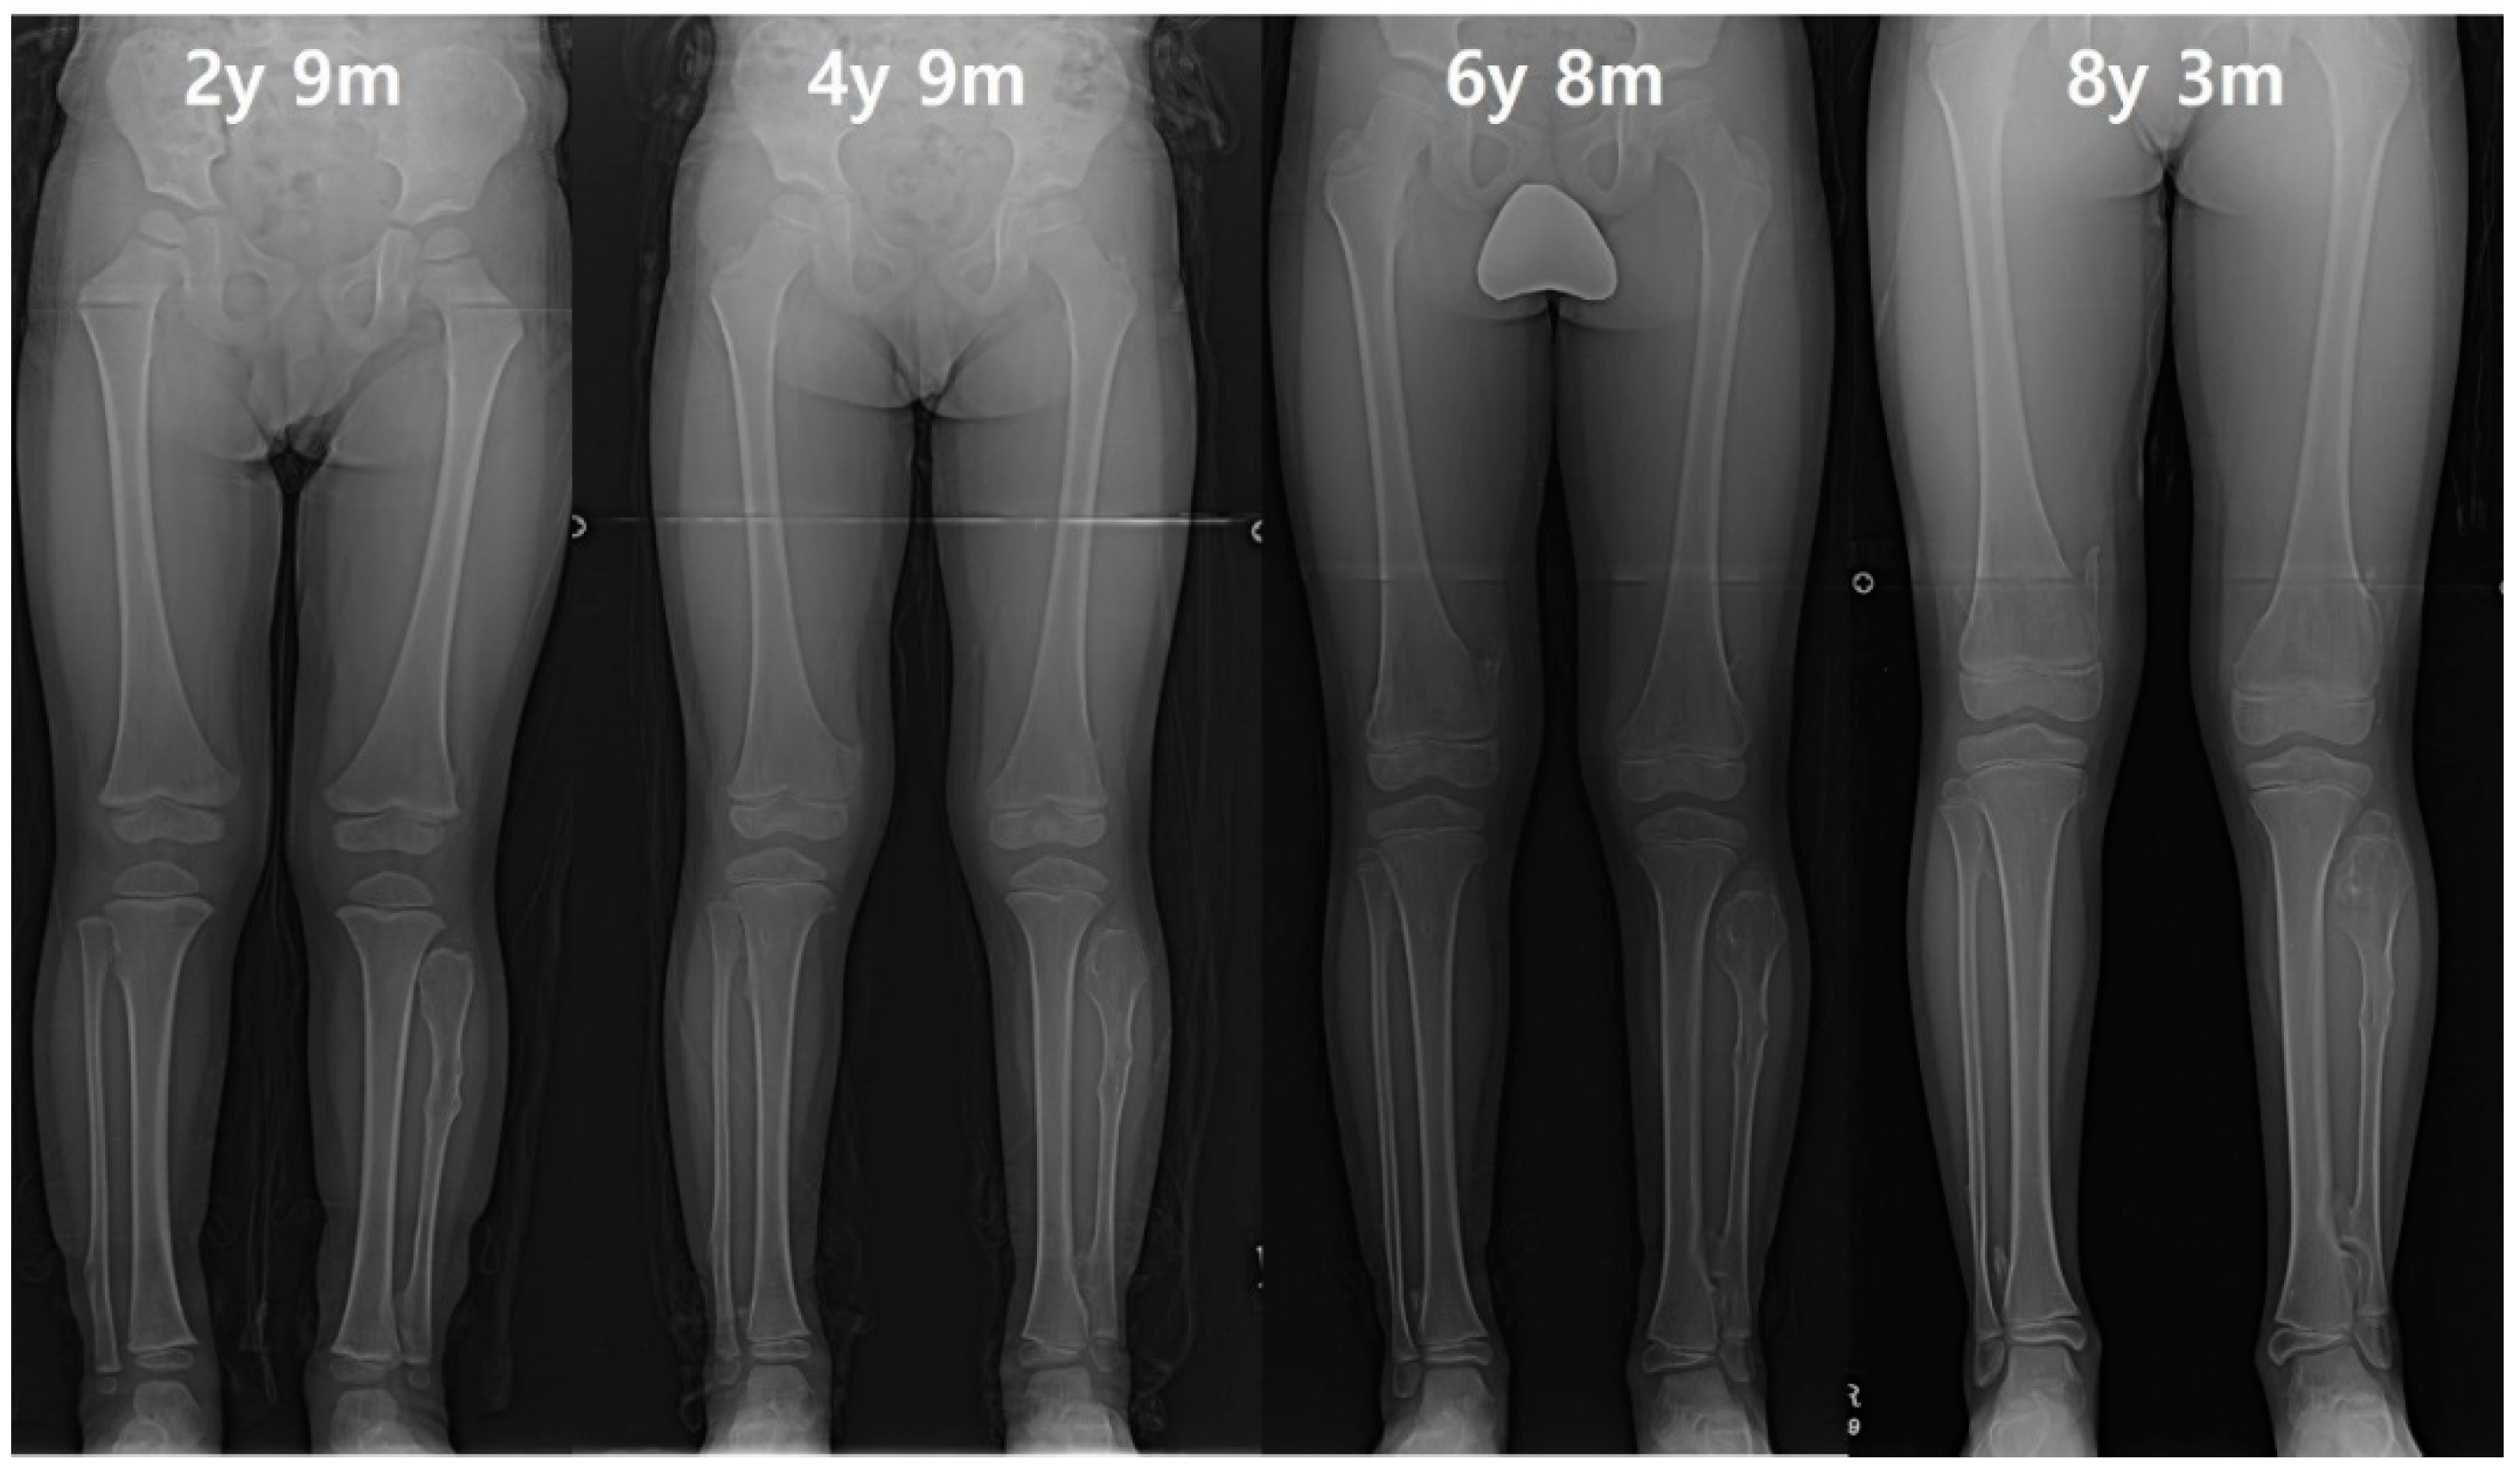

Figure 1. (A) The distance of proximal epiphyses (D) and physes (d) between tibia and fibula. The distance of proximal epiphyses was defined as the gap between the parallel line past the apex of the proximal fibula and the parallel line past the center of the distance between the line across the apex of the tibial spine and the most bottom of the condyle. The distances of proximal physes was defined as the gap between the parallel line passing through the midpoint of the distance between the line across the top of physis; the line crossing the bottom of physis was set as the reference line. (B) The measurement of the ankle joint. The tibiotalar angle was defined as the extension line of the tibial anatomical axis and a line perpendicular to the extension line that touches the dome of the talus. The left lower extremity indicated by the white arrow demonstrates a decreased distal tibiofibular distance compared to the right side, and a prominent ankle valgus deformity is also observed. (C) The tibiofibular synostosis. The white arrow indicates a definite bridge of an exostosis lesion connecting the proximal fibula and tibia without the overlapping cortex.